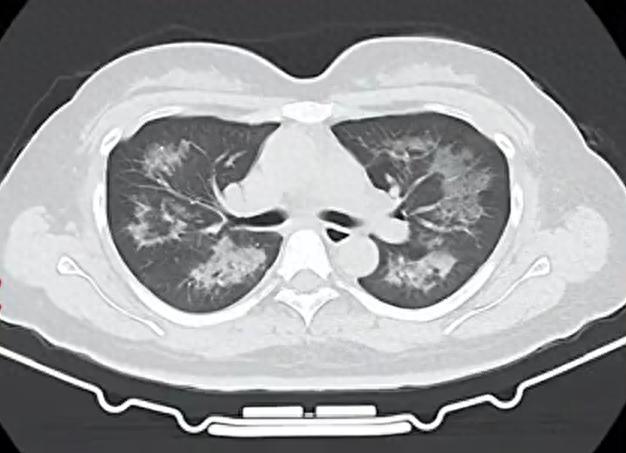

胸部CT進一步顯示,她的雙肺出現多發斑片狀模糊影,被診斷爲間質性肺炎。醫生判斷,病因很可能與她近期長期接觸的某類物質相關。經過反覆細緻地詢問病史,小江才說出自己長期、頻繁使用定妝噴霧的習慣。